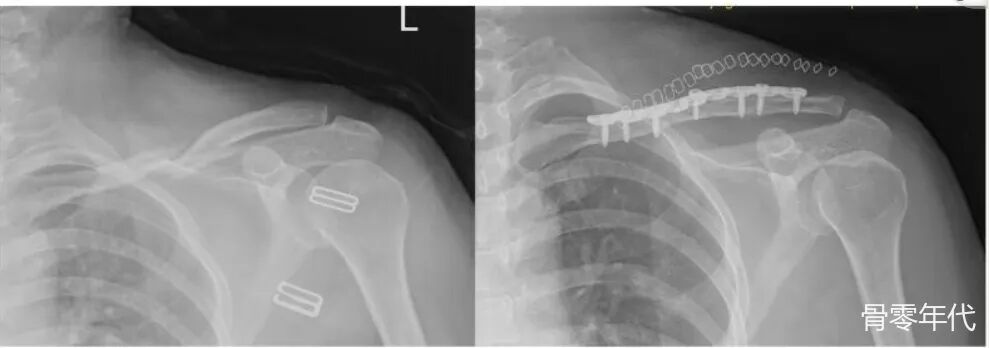

患者,女,47岁,她因骑自行车时摔倒导致左锁骨中段骨折,被归类为AO/OTA13B型,接受了“切开复位和锁板内固定”,术后17个月,患者来到我院要求拆除内固定。术前X线片显示骨折完全愈合,因此进行了锁骨内固定的移除。手术顺利,手术过程中未发现明显异常。术后第5天,患者主诉锁骨区域明显疼痛,没有任何外力,复查X线片显示锁骨骨折,在螺钉固定所在的位置。患者家属依从性强,与患者及家属深入沟通后,同意再次接受手术。手术中,清洗骨折末端后,再次进行锁板内固定,并进行自体髂骨移植。

术前X线检查提示左锁骨中段骨折,移位明显。术后X线:显示内固定到位,骨折对位良好。术后4个月X线片:骨折线仍清晰可见,提示骨折愈合延迟。术后11个月X光片:骨折线仍然清晰可见,这可能表明骨折尚未完全愈合或愈合过程停滞。术后17个月X光片:未见明显骨折线,通常表示骨折已愈合。拆除内固定后:骨折端移位,这意味着发生了骨折。切开复位和骨移植内固定后的X射线。